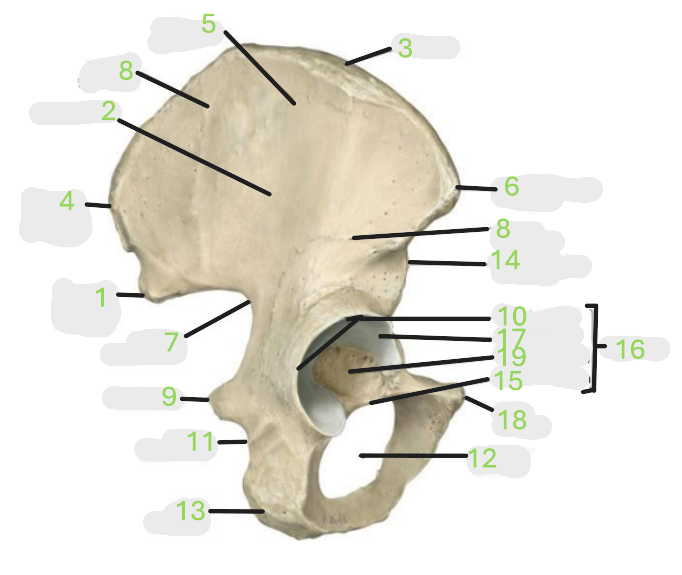

Where is the posterior inferior iliac spine

1

Where is the gluteal surface

2

Where is the iliac crest

3

Where is the posterior superior iliac spine

4

Where is the anterior gluteal line

5

Where is the anterior superior iliac spine

6

Where is the greater sciatic notch

7

Where is the inferior gluteal line

8

Where is the ischial spine

9

Where is the acetabular rim

10

Where is the lesser sciatic notch

11

Where is the obturator foramen

12

Where is the ischial tuberosity

13

Where is the anterior inferior iliac spine

14

Where is the acetabular notch

15

Where is the acetabulum

16

Where is the lunate surface

17

Where is the pubic tubercle

18

Where is the acetabular fossa

19